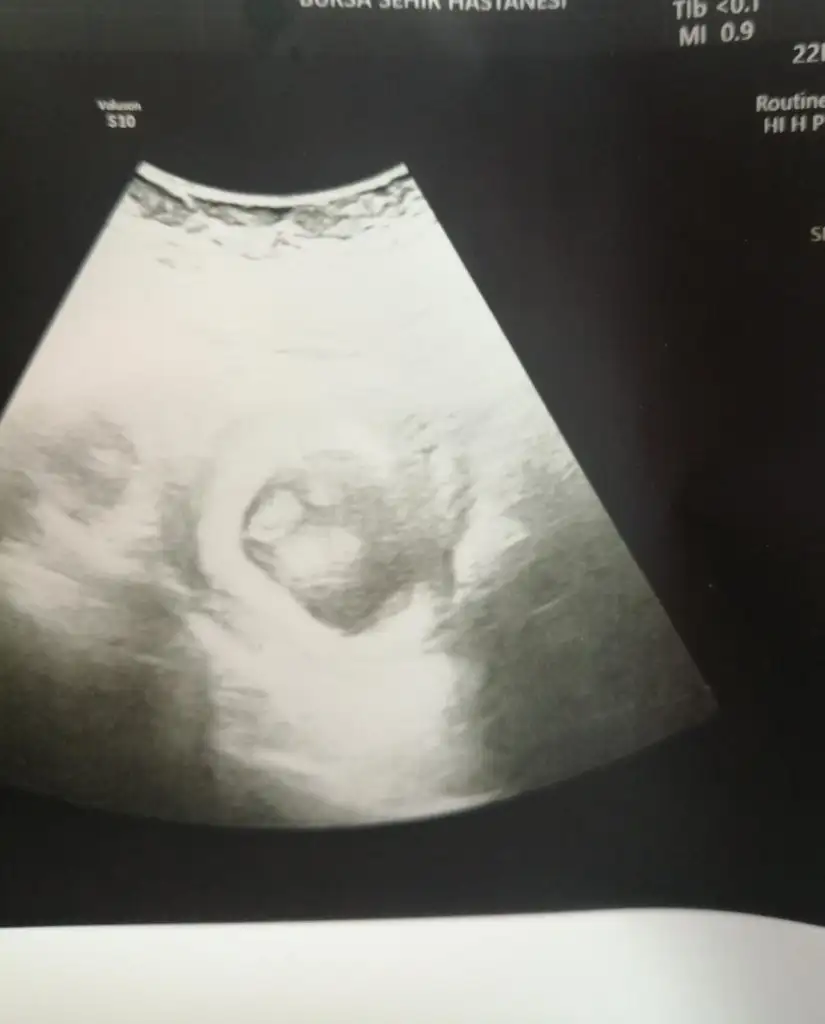

Merhabalar, bende bugun 9+5 im en son kontrole 22 martta gitmiştim ve kendimi zor tutuyorum gitmemek için 🥰 İlk kızımda her hafta dayanamayıp gidiyordum ama bunda daha sakin hareket etmeye çalışıyorum. Benimde diğer hamilelikten farklı olarak bulantım vardı ama bence 9. Hafta civarı bir rahatlama oluyor şuan baya iyiyim çok şükür🙏 Kilo konusunda da bende 1 ile 1.5 kilo arası aldım kesin ama bence çok değil. Herkesin hamilelik süreci farklı geçiyor, benim bulantım varken makarna börek gibi şeyler tükettiğimde iyi geliyordu ve 2 saatte bir karnım acıkıp bulanıyordu. Acı bir tat oluyordu yemediğimde o yüzden az bile almışım😂